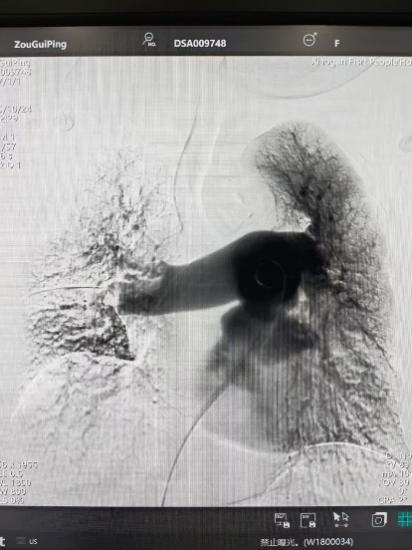

術(shù)后

手術(shù)在局部麻醉下進(jìn)行,團(tuán)隊(duì)通過股靜脈穿刺,將專用抽栓導(dǎo)管精準(zhǔn)送達(dá)肺動脈栓塞部位,利用負(fù)壓抽吸技術(shù)成功清除大量血栓;隨后,在血栓局部精準(zhǔn)灌注溶栓藥物,進(jìn)一步溶解殘余血栓,恢復(fù)肺部血流灌注;同時,為防止下肢深靜脈血栓再次脫落引發(fā)肺栓塞,團(tuán)隊(duì)為患者置入下腔靜脈濾器,整個手術(shù)歷時約1小時。術(shù)后,鄒婆婆呼吸困難癥狀即刻得到緩解,血氧飽和度顯著提升,右心負(fù)荷明顯減輕,目前身體狀況正在逐步恢復(fù)中。